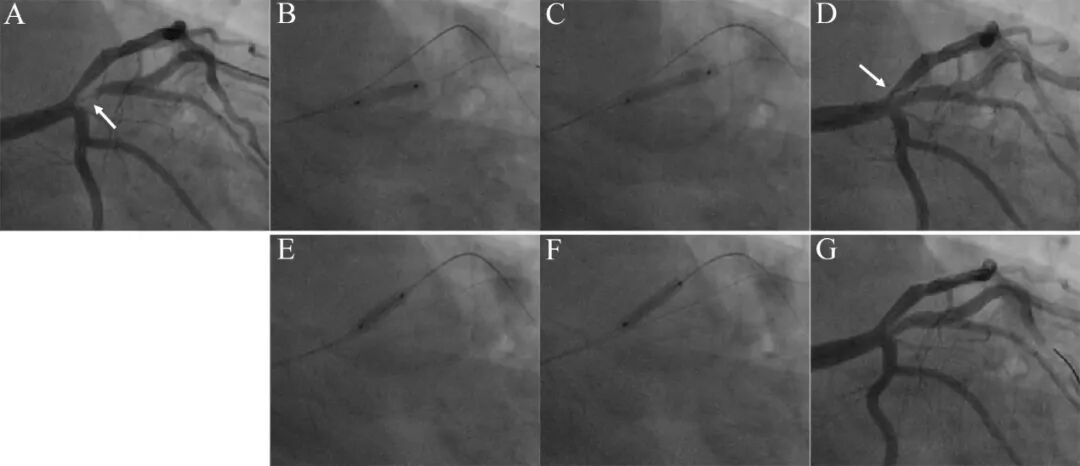

图4 球囊扩张处理中间支开口病变。

55岁吸烟男性,劳力性心绞痛1个月。造影示前降支近段狭窄40%,粗大中间支开口狭窄95%(A)。2.5mm×15mm半顺应性球囊和2.75×10mm切割球囊预处理病变(B),最后2.75×15mm药物球囊10atm×45秒扩张中间支开口病变(C),中间支残余狭窄<50%,但前降支开口狭窄加重(D)。同样流程处理前降支开口病变,先后以2.5×15mm半顺应性球囊、2.75×10mm切割球囊(E)、2.75×15mm药物球囊扩张前降支开口病变(F),造影结果良好(G)。IVUS检查前降支开口和中间支最小管腔面积(MLA)分别为5 mm² 和 4.81 mm²。